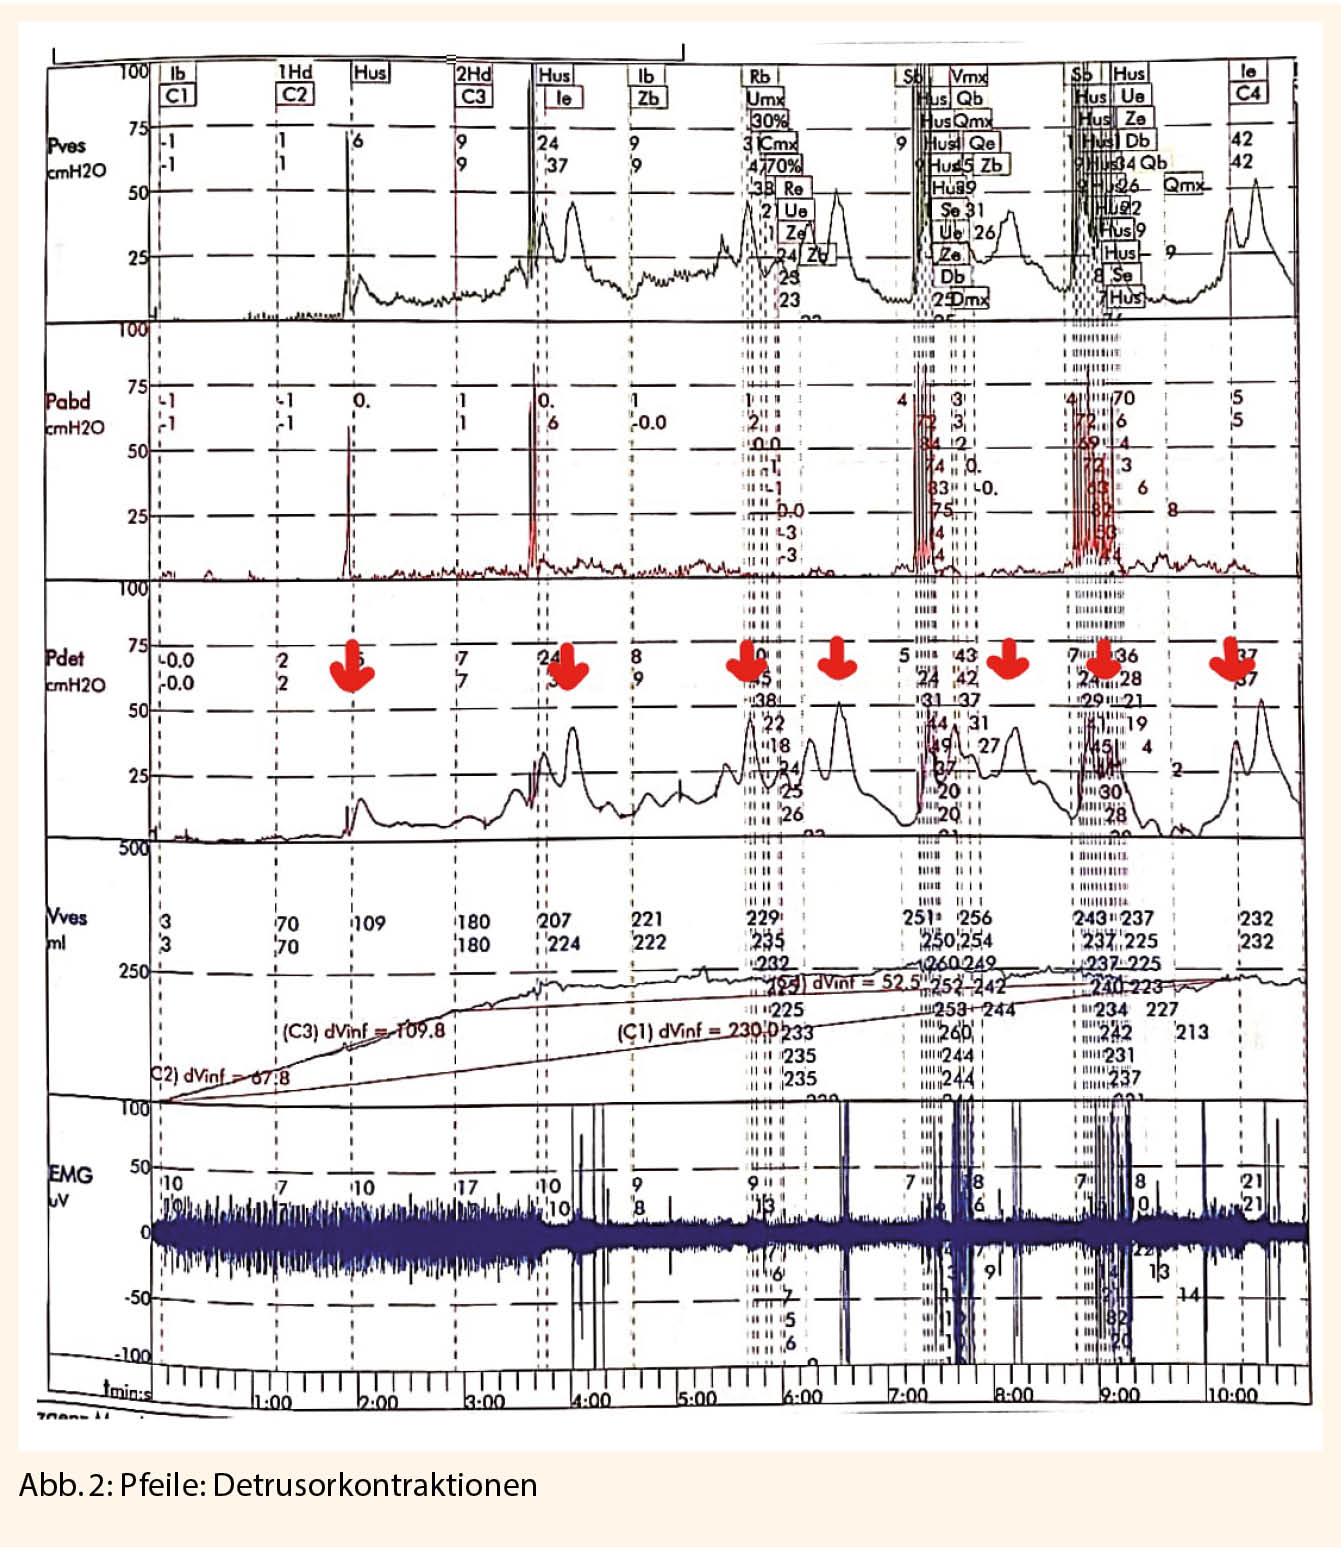

Über den gesamten Untersuchungszeitraum werden kontinuierlich der intravesikale Druck und der abdominelle Druck registriert. Über den transurethralen Katheter wird der intravesikale Druck gemessen. Durch eine rektale Sonde registriert man den abdominellen Druck. Der Detrusordruck wird aus der Differenz von intravesikalem und abdominalem Druck hergeleitet (Pves – Pabd = Pdet). Der Normalbefund ist ein gehemmter Detrusor während der Füllung ohne Zeichen der Kontraktionen. Werden Detrusorkontraktionen aufgezeichnet, ist es wichtig den möglichen Auslöser wie zum Beispiel Hustenstoss, Bewegung, spontan sowie die Höhe der Kontraktion und den Füllungszustand der Blase zu dokumentieren. Ungewollte Detrusorkontraktionen (Abb. 2) sind häufig bei Patientinnen mit Drangbeschwerden nachweisbar.

Während der Harnblasenfüllung wird das Empfinden des Patienten dokumentiert: erster Harndrang (normal ab 200 ml) und unaufschiebbarer Harndrang (normal erst kurz vor der Harnblasenkapazität) (Tab. 2).

Die Dehnbarkeit der Harnblase wird aus dem Quotienten der Differenz der Volumenänderung und Differenz der Detrusordrücke nach Formel Compliance = ΔVolumen ves/ ΔDruck ves errechnet.

Die Compliance sollte über 20cm H2O sein. Ein intravesikaler Druck am Ende der Füllungsphase über 40 cm H2O ist abklärungsbedürftig, weil der obere Harntrakt gefährdet sein kann.